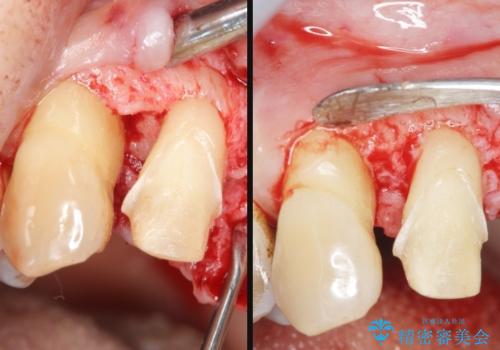

[エムドゲイン] 骨の再生を行った歯周病治療

- 歯周病による歯の疼きを自覚され来院されました。

X線や歯周組織検査の結果歯周病と診断し、エムドゲインを用いた歯周外科手術による骨の再生を図ります。

歯周病により溶けてしまった歯を支える歯槽骨は、エムドゲインを用いた再生治療を行うことで回復させることができることもあります。

通常再生治療後に歯周ポケットが残存した場合、再度ポケット除去手術を行い歯周病の状態を改善しますが今回は歯周ポケットがなく出血もなかったことからジルコニアクラウンを用いて補綴を行いました。